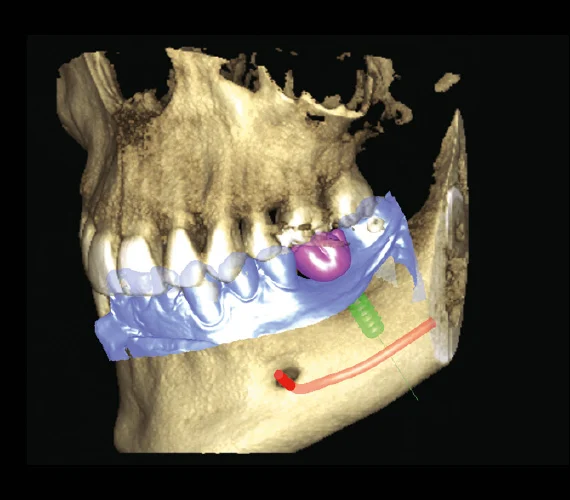

See every detail of your smile with advanced 3D imaging technology. Planmeca ProMax® 3D CBCT allows our dentists to visualize your teeth, jaw, nerves, sinuses, and bone structure in one highly accurate scan to ensure precise diagnosis and treatment planning.

It combines 3D imaging with 2D panoramic and cephalometric scans in a single unit, providing comprehensive diagnostics for implantology, orthodontics, and oral surgery. This system is designed with patient safety in mind, offering precise imaging with low radiation exposure.

Dental Applications of Planmeca ProMax® CBCT:

Planmeca CBCT (Cone Beam Computed Tomography) is an advanced 3D imaging system that captures highly detailed views of your teeth, jaw, bone, nerves, and sinuses in a single scan. It allows our dentists to diagnose and plan treatment with exceptional accuracy.

Traditional X-rays only show flat, 2D images. Planmeca CBCT creates a full 3D digital model of your mouth. This allows dentists to see hidden problems such as bone loss, infections, nerve locations, impacted teeth, and root fractures that regular X-rays can’t detect.